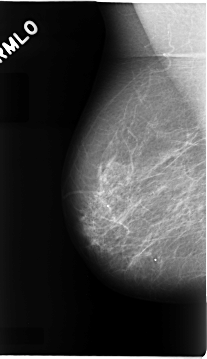

C_0072_1.RIGHT_MLO

RIGHT_MLO LINES 4656 PIXELS_PER_LINE 2688 BITS_PER_PIXEL 12 RESOLUTION 50 NON_OVERLAY